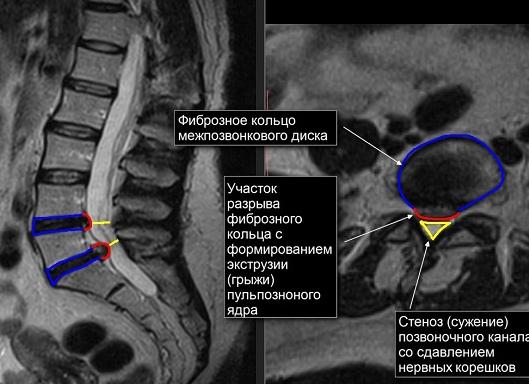

Самая частая проблема поясничного отдела – это грыжи. Стандартная их локализация – место соединения пятого спинного и первого поясничного позвонка.

проблемы, возникшие в межпозвоночных дисках, например защемление нервов, разрывы диска, воспаление седалищного нерва;область позвоночника с аномальным сужением каналов (стеноз), что является возможным показанием к оперативному вмешательству;доброкачественные образования (гемангиомы), развивающиеся в теле позвонков;влияние на нервы и кости позвоночника злокачественных опухолей других близлежащих органов или их метастаз;межпозвонковые грыжи и протрузии дисков в этой области;артрит (воспаленные суставы), а также потерю костной массы;стеноз спинномозгового канала (его сужение);спондилит (дегенеративные изменения позвонков);области с плохим кровоснабжением;инфекционные процессы на уровне поясничного отдела;повреждение нерва вследствие травмы или заболевания, например, рассеянного склероза;врожденные аномалии в развитии позвоночника.

Межпозвоночная грыжа — это патология, при которой диагностируется смещение дисков между позвонками в результате нарушения целостности фиброзного кольца.

Как выглядит патология на результативном МРТ-снимке? Рентгенолог замечает небольшой выступ из межпозвоночного пространства. Чем более запущено заболевание, тем больше это выпячивание.